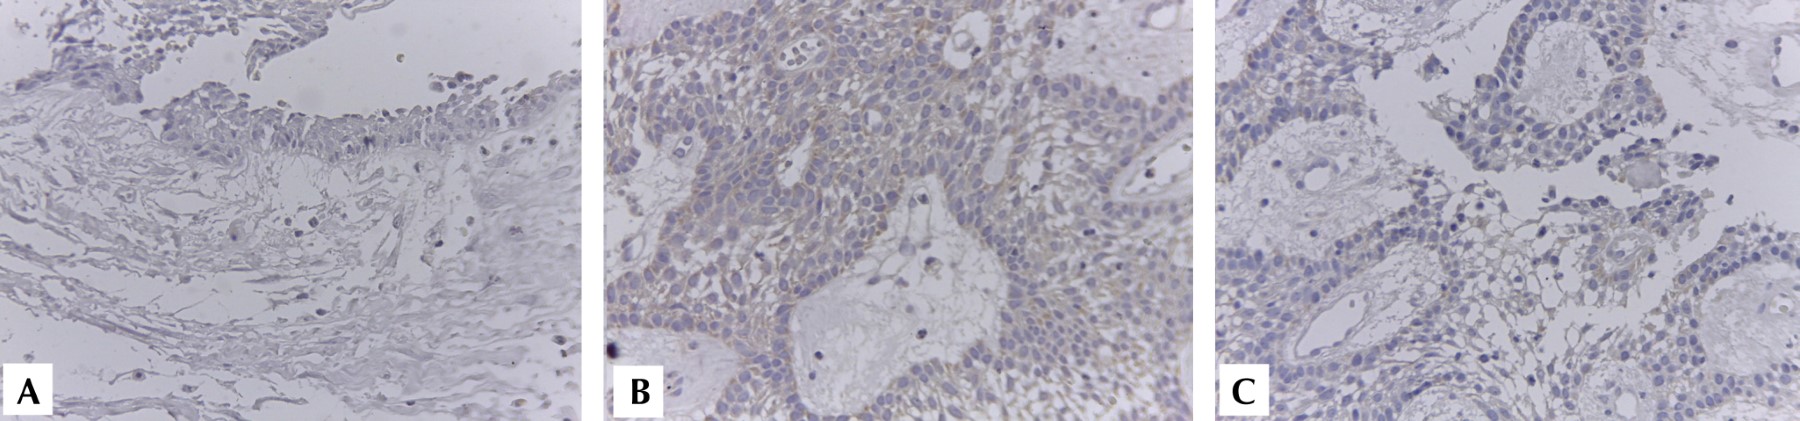

ANáLISIS INMUNOHISTOQUíMICO

En el análisis inmunohistoquímico se observó expresión positiva sólo en uno de los cinco especímenes de AMC, para las MMP-2 y MMP-9. La intensidad observada para MMP-2 fue moderada con proporción de 100% de las células ameloblásticas y del retículo estrellado; el estroma fue negativo. Para MMP-9 observamos un patrón similar al anterior. En el grupo control no observamos presencia positiva de ninguna de las MMP analizadas (Figura 2).

Diversos estudios consideran que el comportamiento localmente agresivo del AMC, no sólo por la capacidad de proliferación del parénquima tumoral, sino también por las enzimas capaces de modificar la MEC, podrían llevar a cabo la remodelación de la matriz ósea, permitiendo la diseminación a través del hueso y los tejidos blandos.15-17 Este es el papel crucial de las MMP en la remodelación y degradación de la matriz extracelular. La producción de MMP se induce en condiciones o estados donde se encuentre presencia de citocinas, factores de crecimiento, hormonas u oncogenes que promuevan la proliferación celular, por lo cual el ameloblastoma puede tener presencia de estas moléculas. En la familia de las metaloproteinasas, la MMP-2 y MMP-9 son consideradas gelatinasas y son capaces de escindir el colágeno IV presente en la membrana basal de los vasos sanguíneos.18,19 La modificación la membrana basal de los vasos sanguíneos es un proceso necesario para la angiogénesis, no obstante, al considerar la presencia tumoral, esto podría significar una potencial vía de diseminación metastásica si la neoplasia alcanza otras características que le permitan migrar. En nuestro análisis inmunohistoquímico únicamente tuvimos inmunoexpresión positiva a MMP-2 y MMP-9 en una sola muestra con patrón plexiforme, lo cual nos sugiere la necesidad de tratar de analizar otras variables tales como el grado de vascularización del tumor o en un escenario negativo la búsqueda de posibles metástasis, para lo cual es necesario realizar más estudios.